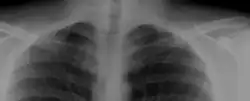

Zespół żebra szyjnego (zespół Naffzigera) – zespół objawów spowodowanych stosunkowo rzadką wadą rozwojową, której częstość w populacji szacowana jest na ok. 1%[1], polegającą na obecności nieprawidłowego wyrostka kostnego (żebra dodatkowego) i ewentualnie jego połączenia z pierwszym żebrem zrostem kostnym lub włóknistym. Nieprawidłowa struktura może traumatyzować splot ramienny i (lub) tętnicę podobojczykową, dając objawy neuropatyczne i (lub) wynikające ze zmniejszonego przepływu krwi przez światło tętnicy. Są to: parestezje, ból zlokalizowany w okolicy dodatkowego żebra, zaniki mięśniowe, niedowład mięśni unerwianych przez nerwy wychodzące z urażanych części splotu. Leczenie polega na resekcji nieprawidłowego żebra wraz z okostną z dostępu nadobojczykowego[2].